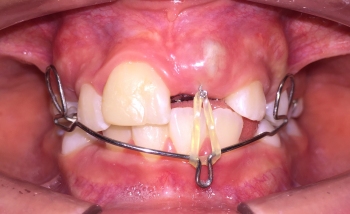

Existen innumerables situaciones clínicas localizadas que se dan tanto en dentición temporal como en época de recambio, que pueden ser fácilmente solucionadas utilizando una amplia gama de aparatogia tanto fija como removible, a fin de evitar que estas se establezcan en forma definitiva y ocasionen mayores dificultades en el futuro.